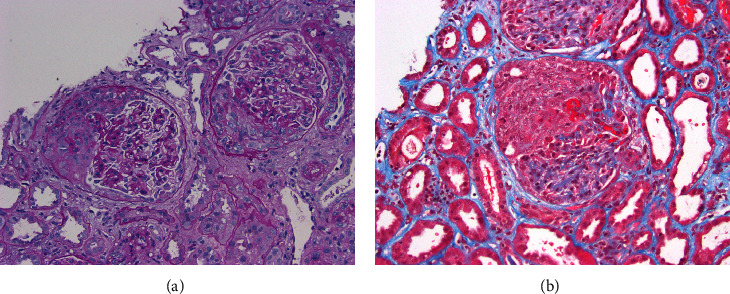

Kidney complications can occur due to infective endocarditis, one of which is glomerulonephritis. Most often, an immune complex or complement-mediated glomerulonephritis is seen on kidney biopsy. In a minor subset of cases, pauci-immune glomerulonephritis may be present. Most often, such patients will demonstrate the presence of antineutrophil cytoplasmic antibodies (ANCA) on serologic testing. A growing number of cases of ANCA-associated glomerulonephritis due to Bartonella endocarditis have been reported. This type of endocarditis can present diagnostic difficulties given that these patients are often culture negative. Herein, we report a challenging case of ANCA-negative pauci-immune glomerulonephritis showing florid crescents on biopsy that was associated with Bartonella endocarditis.